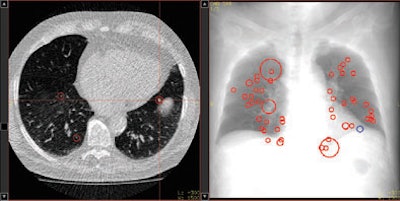

| Above, axial CT image in standard-dose CT (SD-CT) showing a nodule in juxtadiaphragmatic location missed by CAD-1. Above right, CAD markers resulting from the analysis of the SD-CT data presented in a coronal view. Below, CAD analysis of the ultralow-dose CT (ULD-CT) data resulted in automated detection of the corresponding nodule in the left lower lobe. On the right, CAD markers resulting from the analysis of the ULD-CT data. All images courtesy of Dr. Valentina Romano. |

Median false-positive rates per patient were five for CAD-1 versus six for CAD-2 with SD-CT. For ULD-CT, rates were eight for CAD-1 and three for CAD-2.

After separate statistical analysis of nodules with diameters of 5 mm and larger, detection rates increased to 83% for CAD-1 and 61% for CAD-2 at SD-CT and to 89% for CAD-1 and 67% for CAD-2 at ULD-CT. Overall, for both CAD systems, there were no significant differences between the detection rates for standard-dose and ultralow-dose datasets (p > 0.05).

Still, the number of false positives was highly variable by case, CAD system, and the use of standard or low-dose CT protocols.

"In case 21, CAD-1 found more than 25 false-positive nodules in a standard-dose CT scan," Romano said. "If we look at the ultra-low-dose results for CAD-2 [in the same case], there were absolutely no false-positive findings. In another example, there were more than 35 false-positive findings in CAD-1 in the ultra-low-dose dataset and only five false positives using standard dose for both CAD systems."